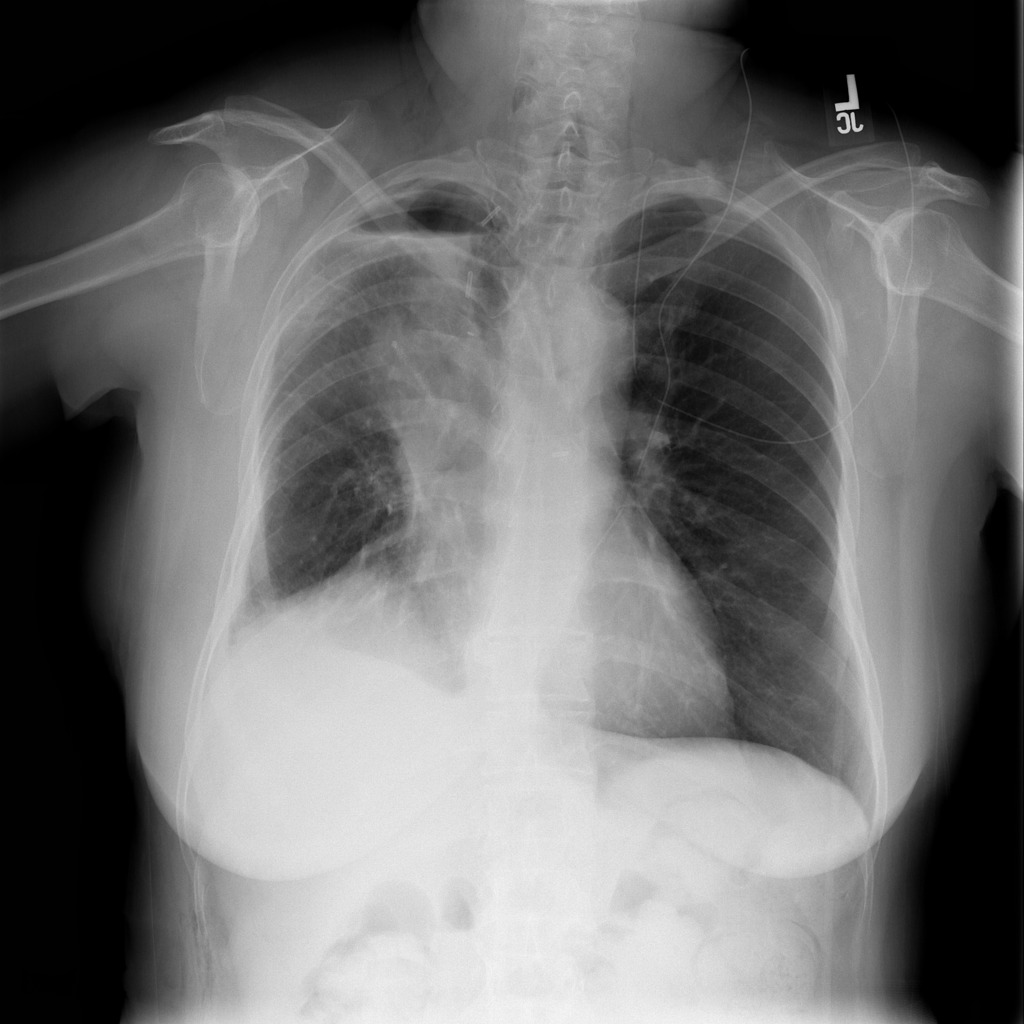

SIIM-ACR Pneumothorax [28] is a competition that provides an open dataset of chest X-ray images with pixel-wise annotation for regions affected by Pneumothorax: a collapsed lung, where an abnormal volume of air is formed in the pleural space between the lung and the chest wall. This dataset was formed from a subset of ChestX-ray14 dataset [31], but relabeled by professional radiologists, and additionally annotated on a pixel level. The specified competition has two stages; ground truth labels are provided only for the first, the second is evaluated on the competition website. Thus, we divided images from the first stage into three sets: train, validation and test. Totally, 12,047 frontal-view chest X-ray cases are in the dataset. We use 2,379 positive and 8,296 negative images for training, 145 and 541 for validation, 145 and 541 for the test.

We present method’s explainability via disease localization regions; cf. Figure 1. We provide qualitative results of segmentation on validation images from both datasets in Figure 2 and Figure 3. We show the resulting maps at each step of our method; the figures demonstrate how the performance improves after each step. We achieve comparable results to state-of-the-art method on PASCAL VOC 2012; cf. Table 4.